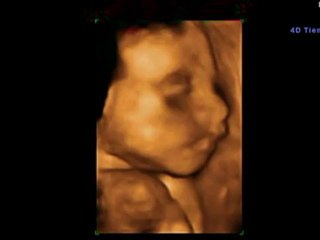

Malaga - 7 semanas pura y simplemente increíble